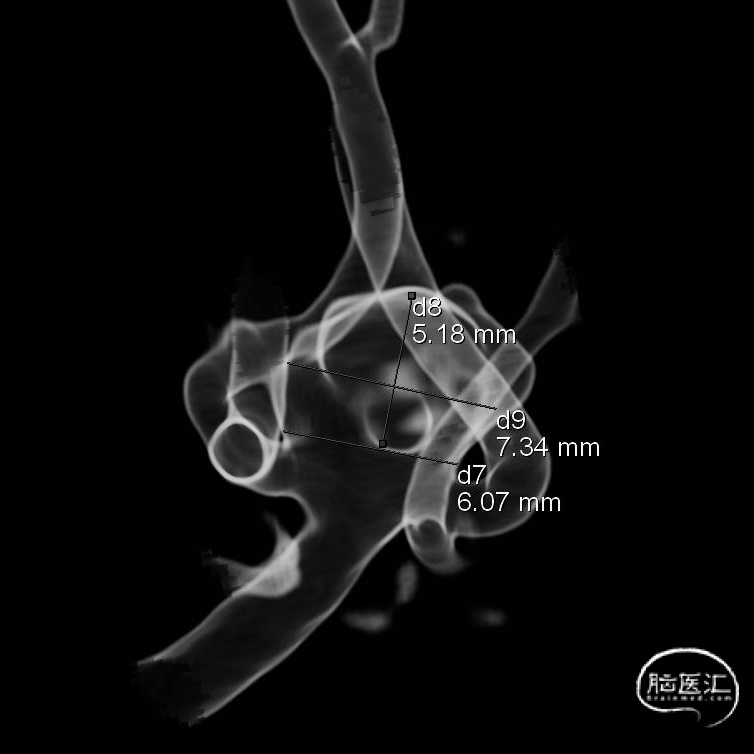

经测量可得动脉瘤宽度平均值为7.0mm,动脉瘤高度为5.18mm,选用WEB™ SL 8*4。

WEB™经由VIA™微导管送入动脉瘤瘤腔并完全释放。术后即刻造影显示WEB™尺寸合适,贴壁良好,分支等血流通畅。解脱后再次造影,可见动脉瘤瘤腔内有明显造影剂滞留。